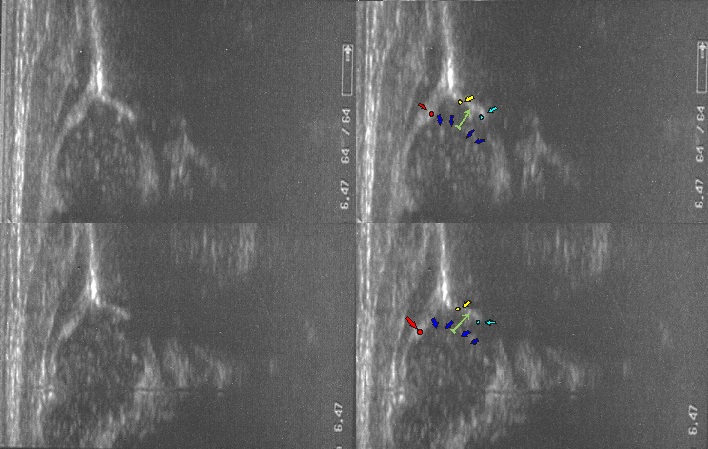

Type IIa+(GN coming to maturity) 6 weeks (below)

the bony roof satisfactory modeling

the bony rim angular but bony roof is only satisfactory ,the first part of bony roof is very good,but the second tail (deeper) is only satisfactory.

the cartilage roof cover the head;

the arrows show labrum (red) ;

the bony rim (yellow);

the lower iliac margin (blue) ,

the bony roof line (blue) is extends tangential to the lower iliac margin and tangent to the bony rim

the cartilage roof line(green) is drown tangential to the bony rim and through the middle point of the labrum echo;

asymmetry in the loose joint capsule; family DDH( when it occurs ask always about it)

the baseline (yellow) is drown parallel to ilium echo through the point of the junction of the perichondrium,the periosseum and ilium.

type I (abow) 6 weeks the bony roof is good

the bony rim blunt

the cartilage roof line(green) is drown tangential to the bony rim and through the middle point of the labrum echo ;

asymmetry in the loose joint capsule ,family DDH( when it occurs ask always about it)

type IIa ( below ) 4 weeks the bony roof is adequate

the bony rim rounded

the bony roof line (green) is extends tangential to the lower iliac margin and tangent to the bony rim

the cartilage roof(blue) is drown tangential to the bony rim and through the middle point of the labrum